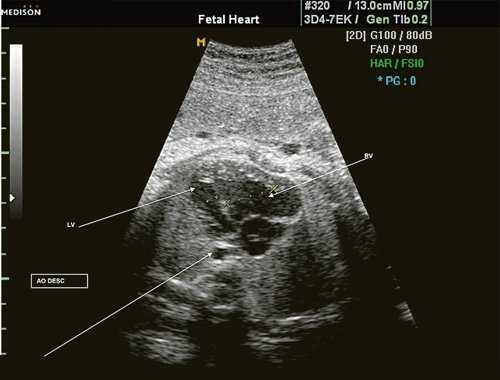

Согласно "теории дуктальной ткани" коарктация аорты возникает в результате миграции гладких мышечных клеток протока в предуктальную аорту, с последующей констрикцией и сужением просвета аорты [4]. При формировании коарктации аорты в области перешейка сохраняется сужение различной протяженности и формы (рис. 2, 3). Наиболее часто это проявляется в виде локальной перетяжки, выше или ниже которой диаметр аорты сохраняется в норме.

Рис. 2. Ультразвуковое исследование восходящего отдела, дуги и нисходящего отдела аорты. Стрелкой указано место сужения.

Рис. 3. Трехмерное изображение сердца и аорты плода в 16 нед беременности. Стрелкой указано место сужения аорты. AO DESC - нисходящий отдел аорты, COR - сердце.

Исходя из особенностей внутрисердечной гемодинамики плода, для диагностики коарктации аорты были предложены косвенные признаки патологии в антенатальном периоде: дилатация правого желудочка и его гипертрофия (см. рис. 3), дилатация легочной артерии [6, 7, 14]. Авторы считают, что это достоверные признаки и встречаются они достаточно часто (в 18 из 24 случаев верифицированных диагнозов коарктации аорты). Поэтому была предложена оценка индексов отношения полости правого желудочка к левому (в норме - 1,1) и легочной артерии к аорте (у здоровых - 1,2). Исходя из увеличения этих параметров, можно предположить наличие затрудненного выброса в аорту или гипоплазию дуги аорты. Тем не менее, по данным предложивших эти косвенные признаки авторов, такие изменения выявляются только в 30% наблюдений (рис. 4).

Рис. 4. Диспропорция размеров желудочков сердца при коарктации аорты. RV - правый желудочек; LV - левый желудочек; AO DESC - поперечное сечение нисходящего отдела аорты.